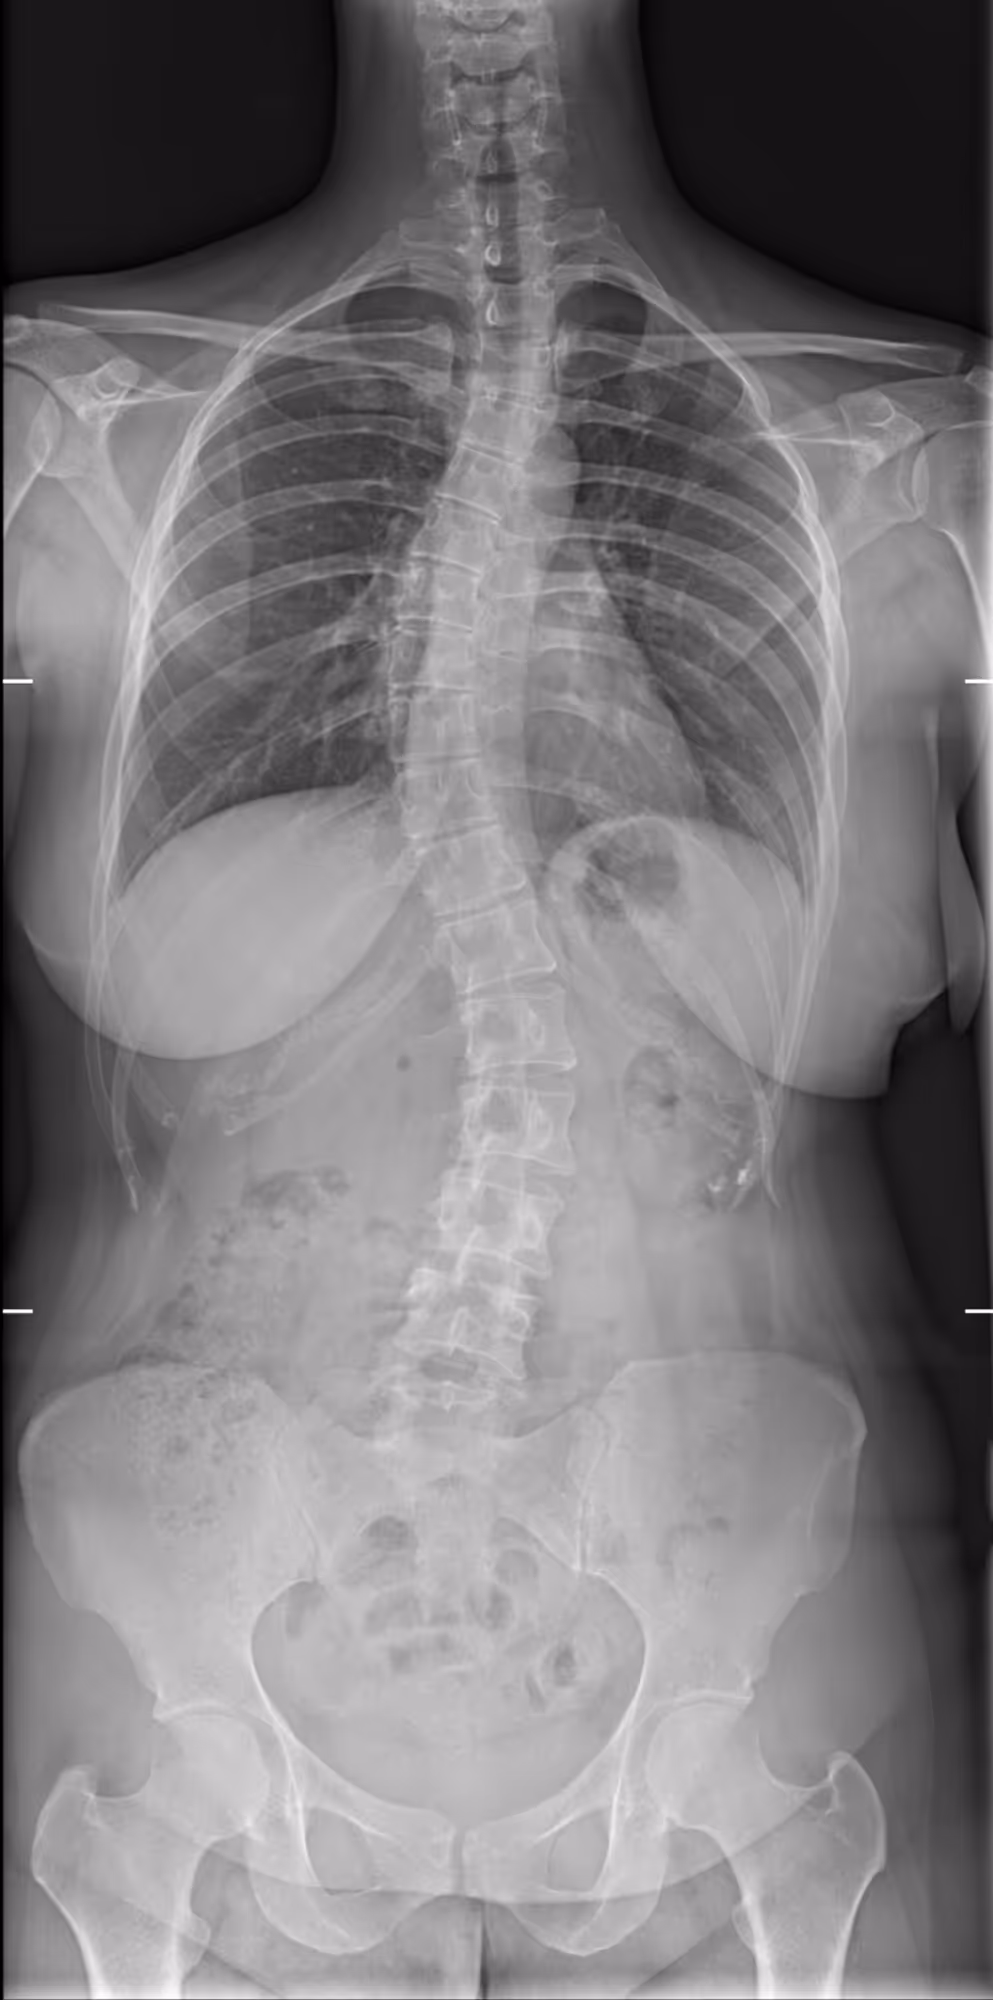

Indication

A 30-year-old female presenting with dorsal main, and a history of untreated scoliosis in childhood.

Results

BoneMetrics identified three distinct Cobb angles, consistent with a triple curve scoliosis.

Frontal

Cobb angle

Pelvic obliquity

Coronal balance

Risser index